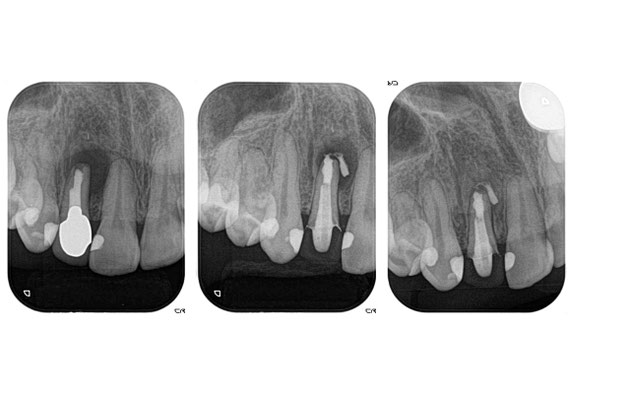

左の写真が治療前の状態です。

患者様は「できるだけ歯を抜きたくない」というご希望で来院されました。

レントゲンで根の先に黒い影が見えますが、これは炎症による像です。

中央の写真:根管治療を行った後の状態です。内部をしっかり消毒し、MTAセメントという特殊な材料で根の先を封鎖しています。

右の写真:治療から約4か月後。根の先の黒い影が小さくなり、骨が回復してきていることが確認できました。炎症が落ち着いたと考えられます。

結果として、歯を抜かずに残すことができました。

レントゲン写真では、骨が吸収して黒い丸い像が見えるようになります。

お写真の上のほうに黒い丸い像は歯の根っこの炎症で骨が吸収してしまった像です。

しっかりと根っこの中の細菌を取り除くことで、骨の吸収が回復することが期待できます。